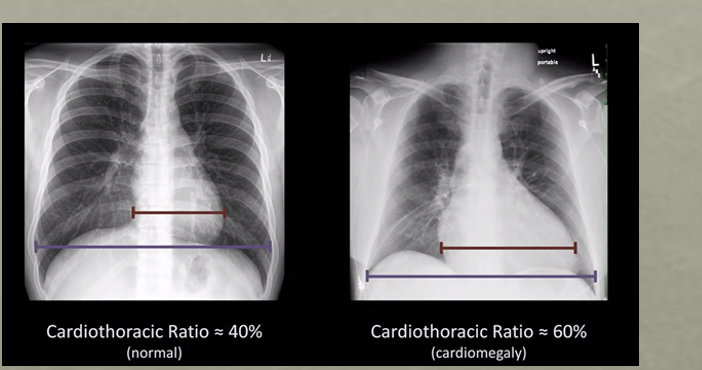

C - Cardiac Silhouette and Mediastinum:

* Normal heart size = <50% of thoracic width (PA) view

* Enlarged heart (>50%) –> cardiomegaly, pericardial effusion

notice the cardiac thoracic ratio